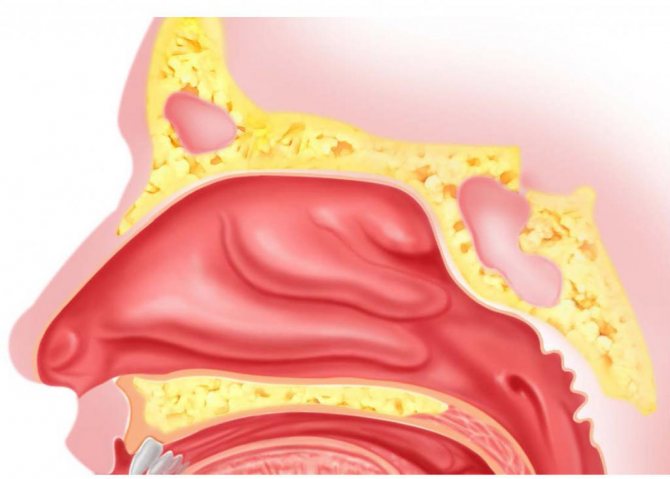

- сприяє відновленню носового дихання і зниження закладеності носа шляхом сприятливого впливу на слизову оболонку носової порожнини і зниження її набряку, обумовлених виведенням з міжклітинної простору зайвої рідини в результаті різниці осмотичного тиску;

- інтенсивно промиваючи всі відділи носоглотки і порожнини носа, зволожує їх слизову оболонку і видаляє віруси, бактерії, алергени, пил, кірки і надлишки слизу;

- активізує захисну дію миготливого епітелію, забезпечує підтримку нормального фізіологічного стану слизової оболонки порожнини носа і носоглотки;

Лікарський засіб Аквалор містить морські мінерали. Завдяки цьому забезпечується активний лаваж носової порожнини: видаляється слиз, зменшуються рідкі виділення, знижується набряк слизової оболонки, розм’якшуються і легко віддаляються кірки.

Завдяки дії морської води, нормалізується функція миготливого епітелію, відбувається поліпшення носового дихання. Морська вода зволожує слизову порожнину, і має протизапальну дію. Після ретельного промивання слизової, краще вбираються і діють різні лікарські засоби.

Завдяки цьому скорочується тривалий перебіг хвороби, знижується ризик появи локальних ускладнень. До того ж, в носових пазухах йде менше поширення інфекції. Відповідно – менший ризик виникнення отиту, фронтіта, гаймориту. При видаленні аденоїдів або поліпів Аквалор зменшує подразнення слизової поверхні носової порожнини, особливо у тих осіб, які піддаються різним шкідливим впливам (водії автотранспорту; курці, люди, що працюють в кондиціонованих приміщеннях, де сухе повітря; працівники запилених цехів).